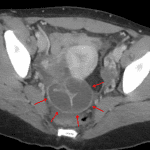

Age: 26

Sex: Female

Indication: Right lower quadrant pain

Findings

- Lower chest

- No acute findings

- Abdomen/Pelvis

- Tubular serpiginous structure with thickened, enhancing walls related to the right adnexa

- Small amout of free fluid layering in the anatomic pelvis

- Normal appendix

Diagnosis

- Pyosalpinx

Findings concerning for right pyosalpinx and possible developing tubo-ovarian abscess.